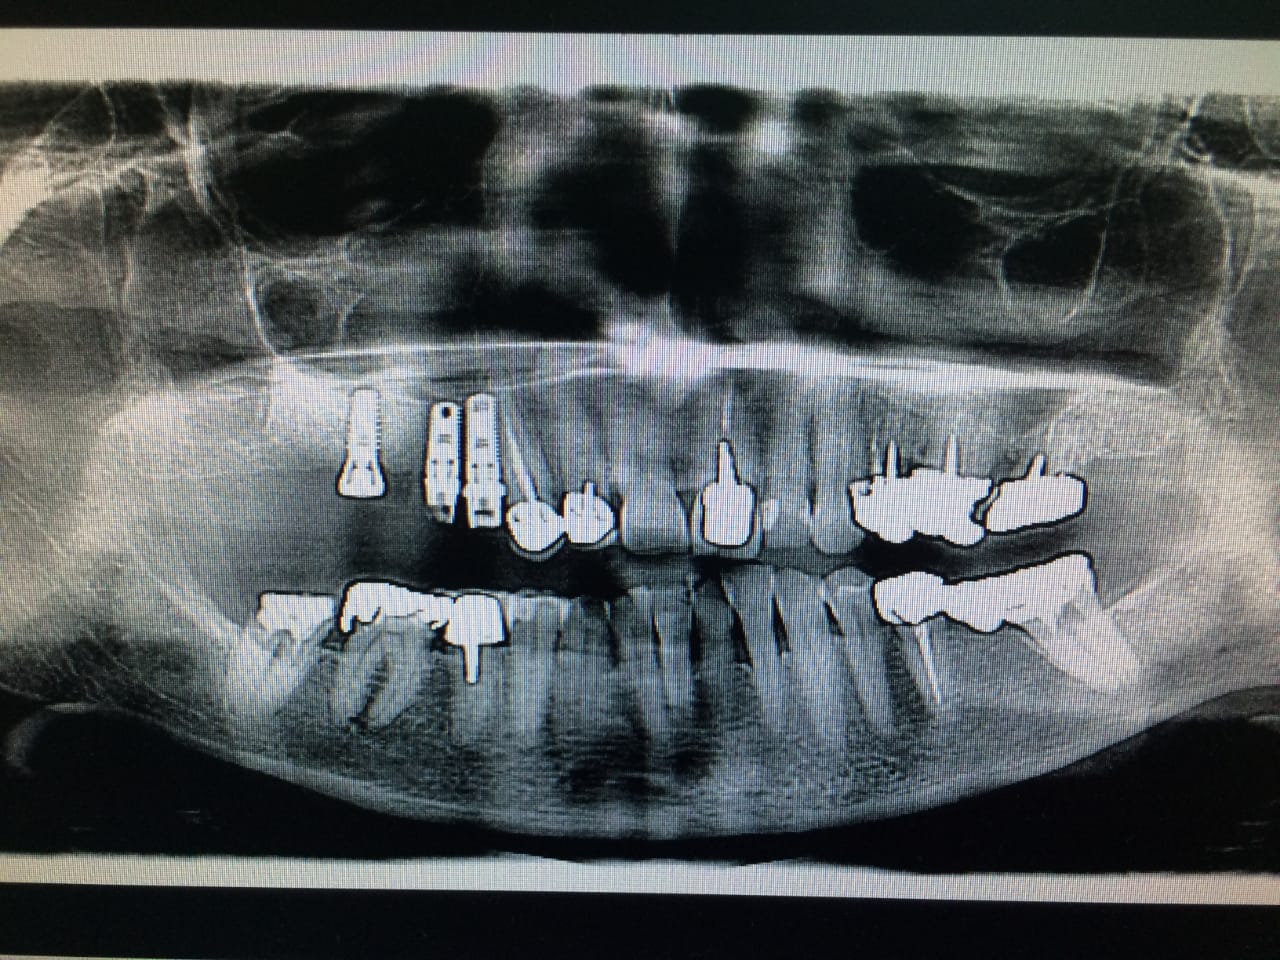

→ Pose du ou des implants

Durant cette étape, le praticien pose les implants dentaires pour remplacer les racines manquantes. À l’issue de cette intervention, vous sentirez des implants couverts par la gencive, et qu’ils sont mis en “nourrice” : cela permet à l’os de cicatriser autour des implants.

Ces dents provisoires sont placées afin de vous permettre de manger et de parler normalement en attendant la mise en place de la prothèse définitive.

→ Pose de la prothèse définitive

Après la cicatrisation de l’os et de la gencive, une simple prise d’empreinte comme sur une dent naturelle permettra la réalisation d’une prothèse naturelle et fonctionnelle.